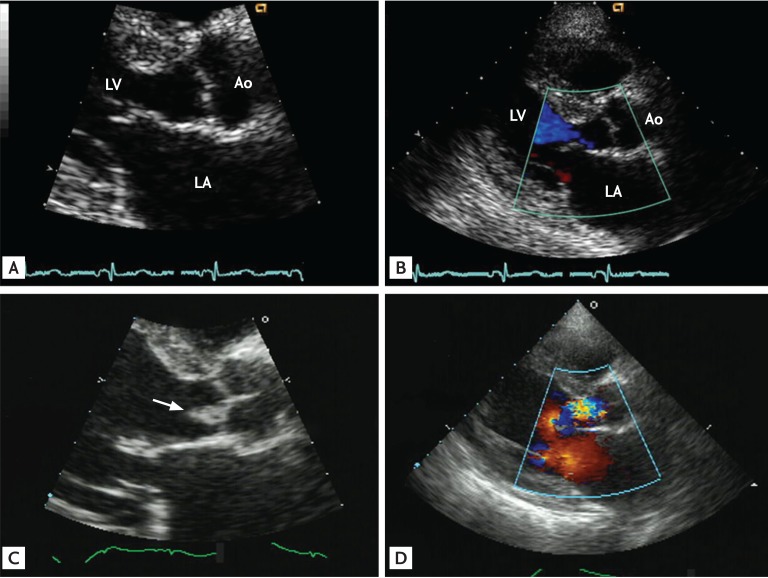

Figure 2

Representative echocardiographic images of a patient with nosocomial healthcare-associated infective endocarditis involving an apparently normal-looking valve. The patient, a 72-year-old male, underwent uneventful surgery for colon cancer, but his recovery was complicated by fever and Staphylococcus aureus bacteremia. Compared with his preoperative echocardiographic images, which showed apparently normal-looking mitral and aortic valves (A-C), follow-up echocardiography showed the development of typical vegetation (arrow) on both the mitral and aortic valves (D-F). Ao, aorta; LA, left atrium; LV, left ventricle.